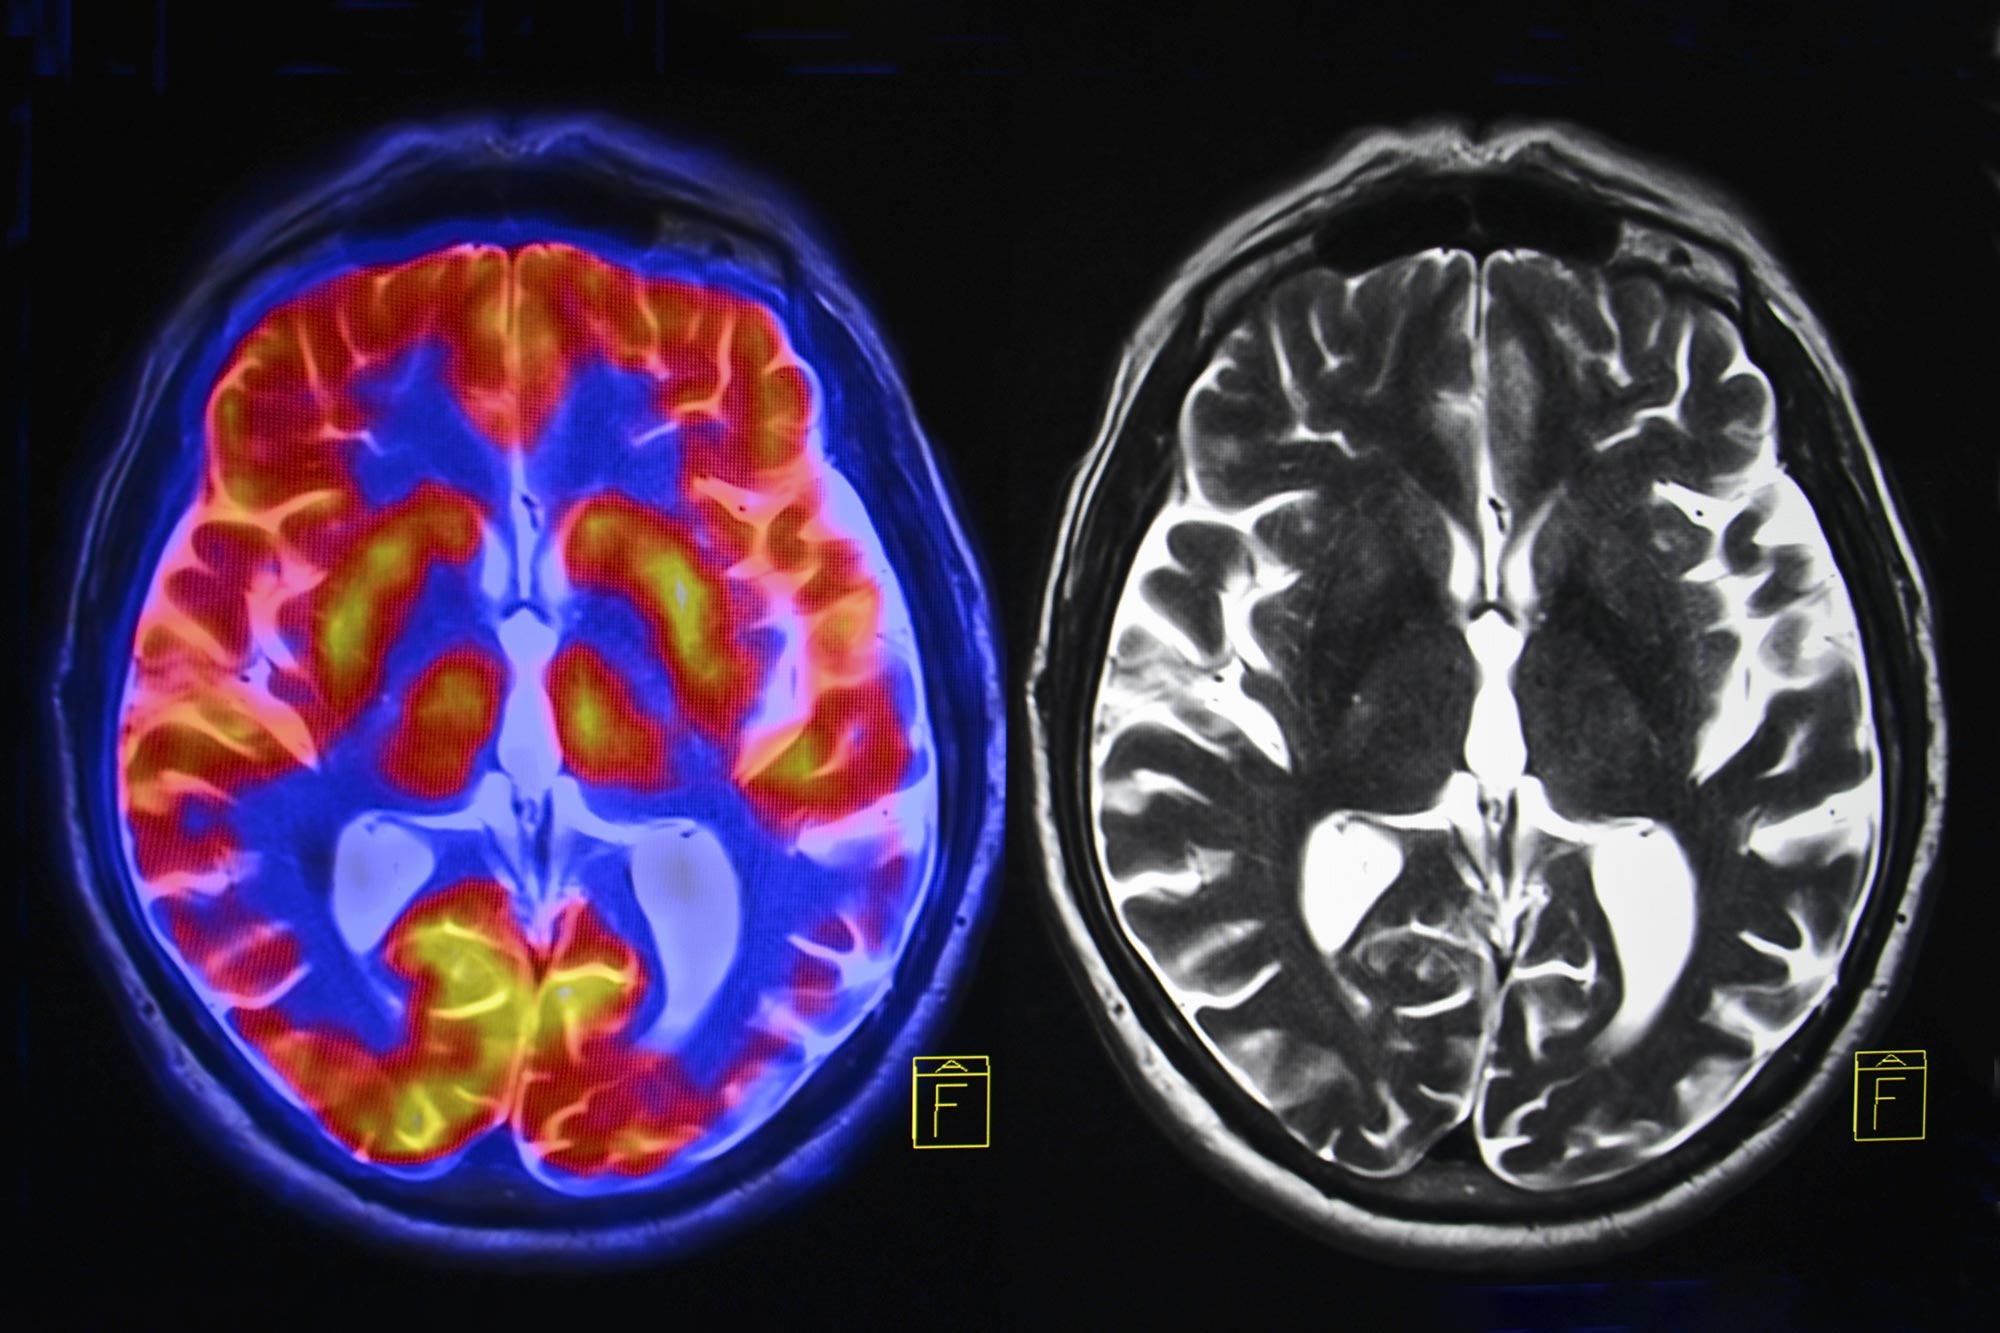

To unravel the complexities of these brain changes, researchers analyzed data from nearly 125,000 women in the UK Biobank. Participants were divided into three groups: pre-menopausal, post-menopausal women who had never used hormone replacement therapy (HRT), and those who had. They filled out questionnaires about their menopausal symptoms, mental health, and lifestyle habits. Some women underwent MRI scans to visualize the actual changes in brain structure.

The results were telling. Women who had gone through menopause exhibited a noticeable reduction in grey matter volume in areas of the brain critically involved in memory and emotional regulation. This finding raises vital questions about the link between menopause and the increased prevalence of mental health issues and cognitive decline.

Perhaps the most striking aspect of this research is the observed loss of grey matter across several critical regions of the brain following menopause. Grey matter, which contains the cell bodies of nerve cells, plays a key role in processing information, regulating movement, and controlling emotional responses.

The hippocampus, crucial for forming and storing memories, alongside regions like the entorhinal cortex and anterior cingulate cortex, showed notable reductions in volume among post-menopausal women. This raises essential questions about long-term cognitive health and the potential risk of dementia. Indeed, the areas affected are commonly associated with Alzheimer’s disease, further compounding concerns about women’s health as they age.